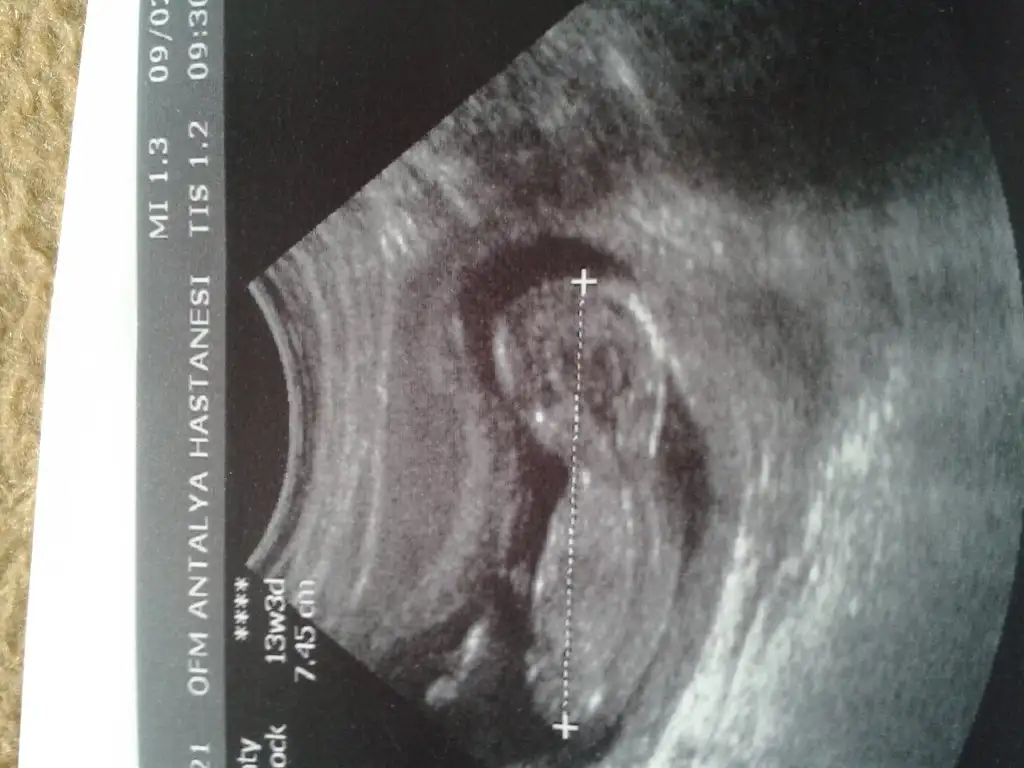

dr soylemeden siz gorun genital nub teorisi ( bebegin cinsiyeti)

kızlar bilenler yardımcı olabilir mi :)

bendee çok merak ediyorum ama tahminim kız net orta da eşimde erkek diye çok heveslendi ama olmayacka gibi 3 hafta sonra ögrenicem

yook belli değil benim nub teorime göre kız :KK64: bide doktorum kıza benziyor dedi. ama kemik gelişimi erkek dedi kesin demiyorum dedi diğer geldiğinize kesinleştiririm dedi.